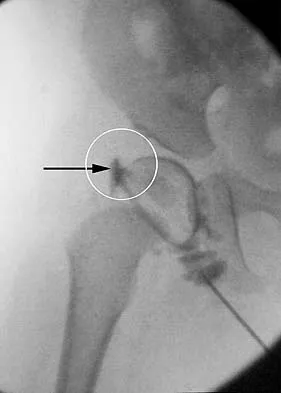

Figure 16a shows the radiograph of a 34-year-old woman who sustained a basicervical fracture of the femoral neck. The fracture was treated with a compression screw and side plate. Seven months postoperatively, she continues to have significant hip pain and cannot bear full weight on her hip. A recent radiograph is shown in Figure 16b. Management should now consist of

Explanation